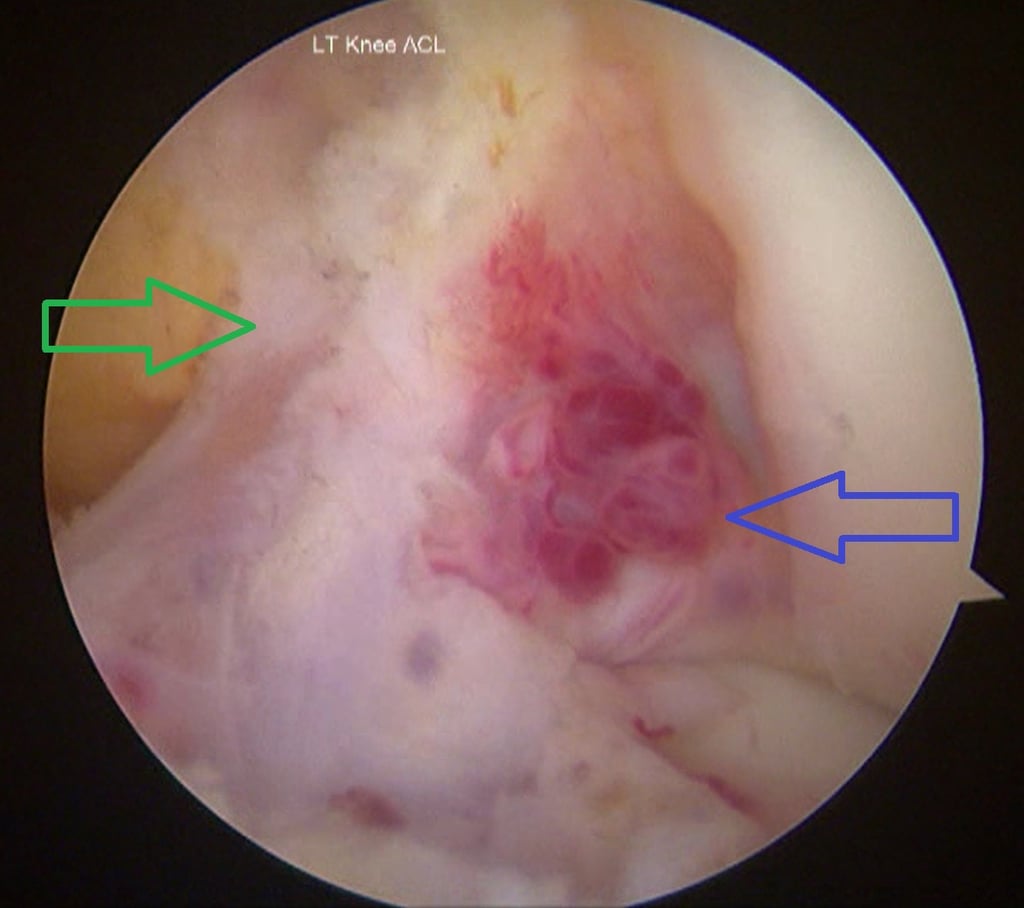

Anterior cruciate ligament haemangioma

Haemangioma involving the ACL is extremely rare. MRI remains the investigation of choice for diagnosis. MRI helps to differentiate these from synovial chondromatosis, pigmented villonodular synovitis and gouty tophi. For a lesion involving the ACL like in our case, the closest differential to be considered was a ganglion cyst involving the ACL. It has a similar shape, size and can involve the ACL. It can be differentiated from ACL haemangioma by a fat-suppressed, contrast-enhanced MRI which shows a thin, rim-enhancing feature of ganglion cysts, or by histopathological examination. The available literature suggests arthroscopic excision as the preferred modality for treatment of ACL haemangioma/intra-articular haemangioma over open resection and synovectomy.